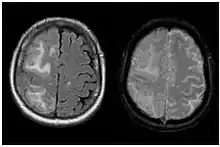

Two MRI scans demonstrating the difference between ARIA-E (left) and ARIA-H in the parietal region (right)

Amyloid-related imaging abnormalities (ARIA) are abnormal differences seen in magnetic resonance imaging of the brain in patients with Alzheimer's disease. ARIA is associated with anti-amyloid drugs, particularly human monoclonal antibodies such as aducanumab.[1] There are two types of ARIA: ARIA-E and ARIA-H. The phenomenon was first seen in trials of bapineuzumab.[2]